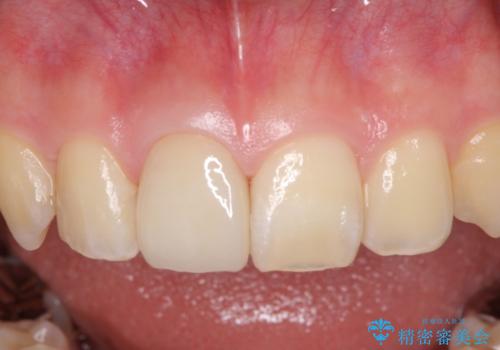

- 治療中の前歯と口腔内にある銀歯が気になるとのことで来院された患者様です。

口腔内の金属が全てなくなり、患者様には大変満足していただきました。